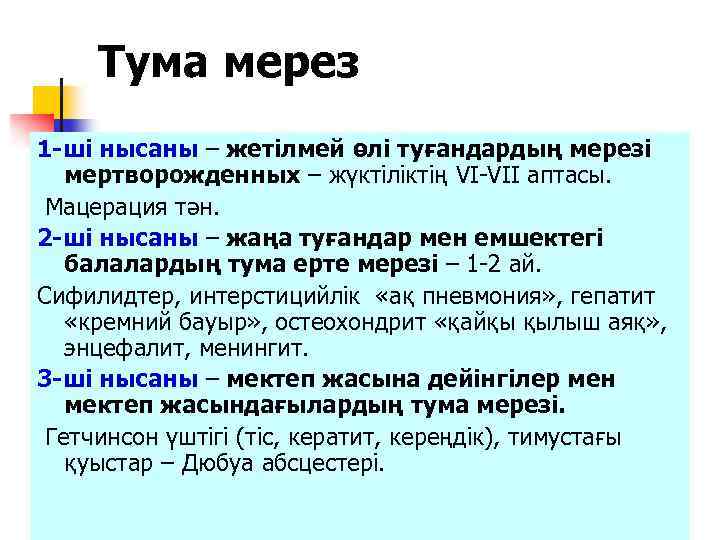

Тума мерез 1 -ші нысаны – жетілмей өлі туғандардың мерезі мертворожденных – жүктіліктің VI-VII аптасы. Мацерация тән. 2 -ші нысаны – жаңа туғандар мен емшектегі балалардың тума ерте мерезі – 1 -2 ай. Сифилидтер, интерстицийлік «ақ пневмония» , гепатит «кремний бауыр» , остеохондрит «қайқы қылыш аяқ» , энцефалит, менингит. 3 -ші нысаны – мектеп жасына дейінгілер мен мектеп жасындағылардың тума мерезі. Гетчинсон үштігі (тіс, кератит, кереңдік), тимустағы қуыстар – Дюбуа абсцестері.